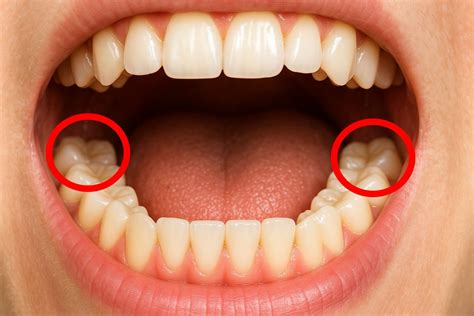

Las muelas del juicio, también conocidas como terceros molares o cordales, a menudo son motivo de preocupación en el mundo dental. Muy similar a la dentición de un bebé, la salida de las muelas del juicio es una experiencia dolorosa. Las muelas del juicio son piezas dentales que, debido precisamente a su ubicación, pueden ocasionar diversos problemas. El más común es la falta de higiene.

El dolor de las muelas del juicio puede deberse a diferentes causas. Al ser los últimos en aparecer, en ocasiones nuestra boca no tiene espacio suficiente para alojarlos y quedan retenidos produciéndonos dolor e hinchazón en esa zona. Otra de las razones para extraerlas es si el maxilar no es lo suficientemente grande o si no hay lugar en la boca para ellas.

Cuando salen estas muelas rompen la encía, lo que hace que una capa de tejido crezca sobre ellas. Si han erupcionado ya las muelas del juicio, debido a su posición en la boca, siendo las últimas de la arcada dentaria, la higiene resulta un poco complicada.